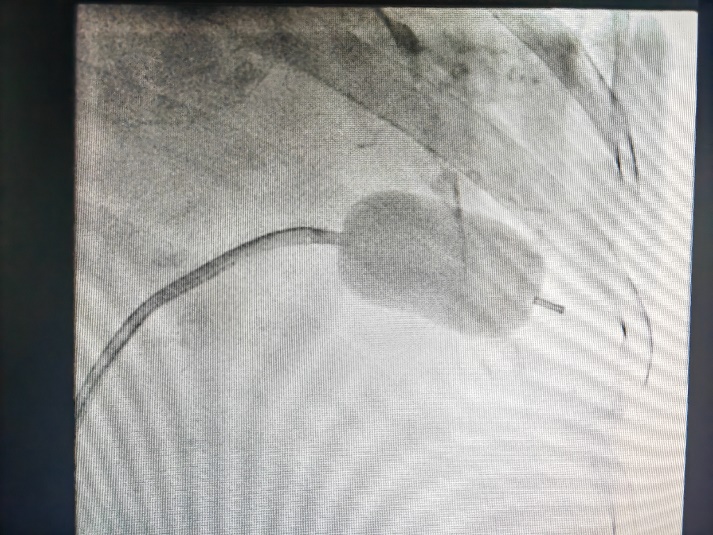

图四:球囊对狭窄的二尖瓣进行扩张

此例手术由姚晓伟主任医师、韩稳琦主治医师、赵永勇主治医师通过心腔内超声指导下进行,通过心腔内超声精准构建心脏模型、直视下穿刺房间隔,后通过心腔内超声及左心房造影寻找狭窄的二尖瓣瓣口,并指引二尖瓣球囊扩张导管顺利经狭窄的二尖瓣口至左心室,在心腔内超声的指引下选择最佳位置以26mm球囊导管反复扩张狭窄的二尖瓣。术后第二天复查心脏超声,患者二尖瓣瓣口面积由术前0.67cm2扩大到术后1.69cm2,二尖瓣跨瓣压差由术前22mmHg降低至术后的16mmHg,左房前后径由术前94mm减小至术后92mm,左房左右径由术前109mm减小至术后102mm,并且球囊扩张后未引起明显的二尖瓣反流,患者心功能明显改善,自觉症状明显好转出院。